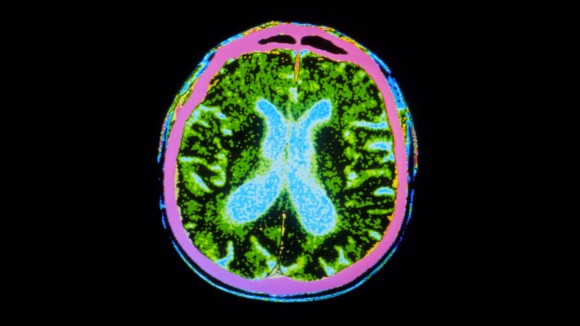

Penyakit Parkinson adalah kondisi neurologis progresif yang disebabkan oleh hilangnya neuron penghasil dopamin, yang menyebabkan tremor, kekakuan, dan kelambatan gerakan. Tidak ada obat untuk kondisi ini, yang diproyeksikan akan mempengaruhi 25 juta orang secara global pada tahun 2050. Terapi sel dirancang untuk menggantikan neuron yang rusak, tetapi uji coba sebelumnya menggunakan transplantasi jaringan janin memberikan hasil yang beragam.